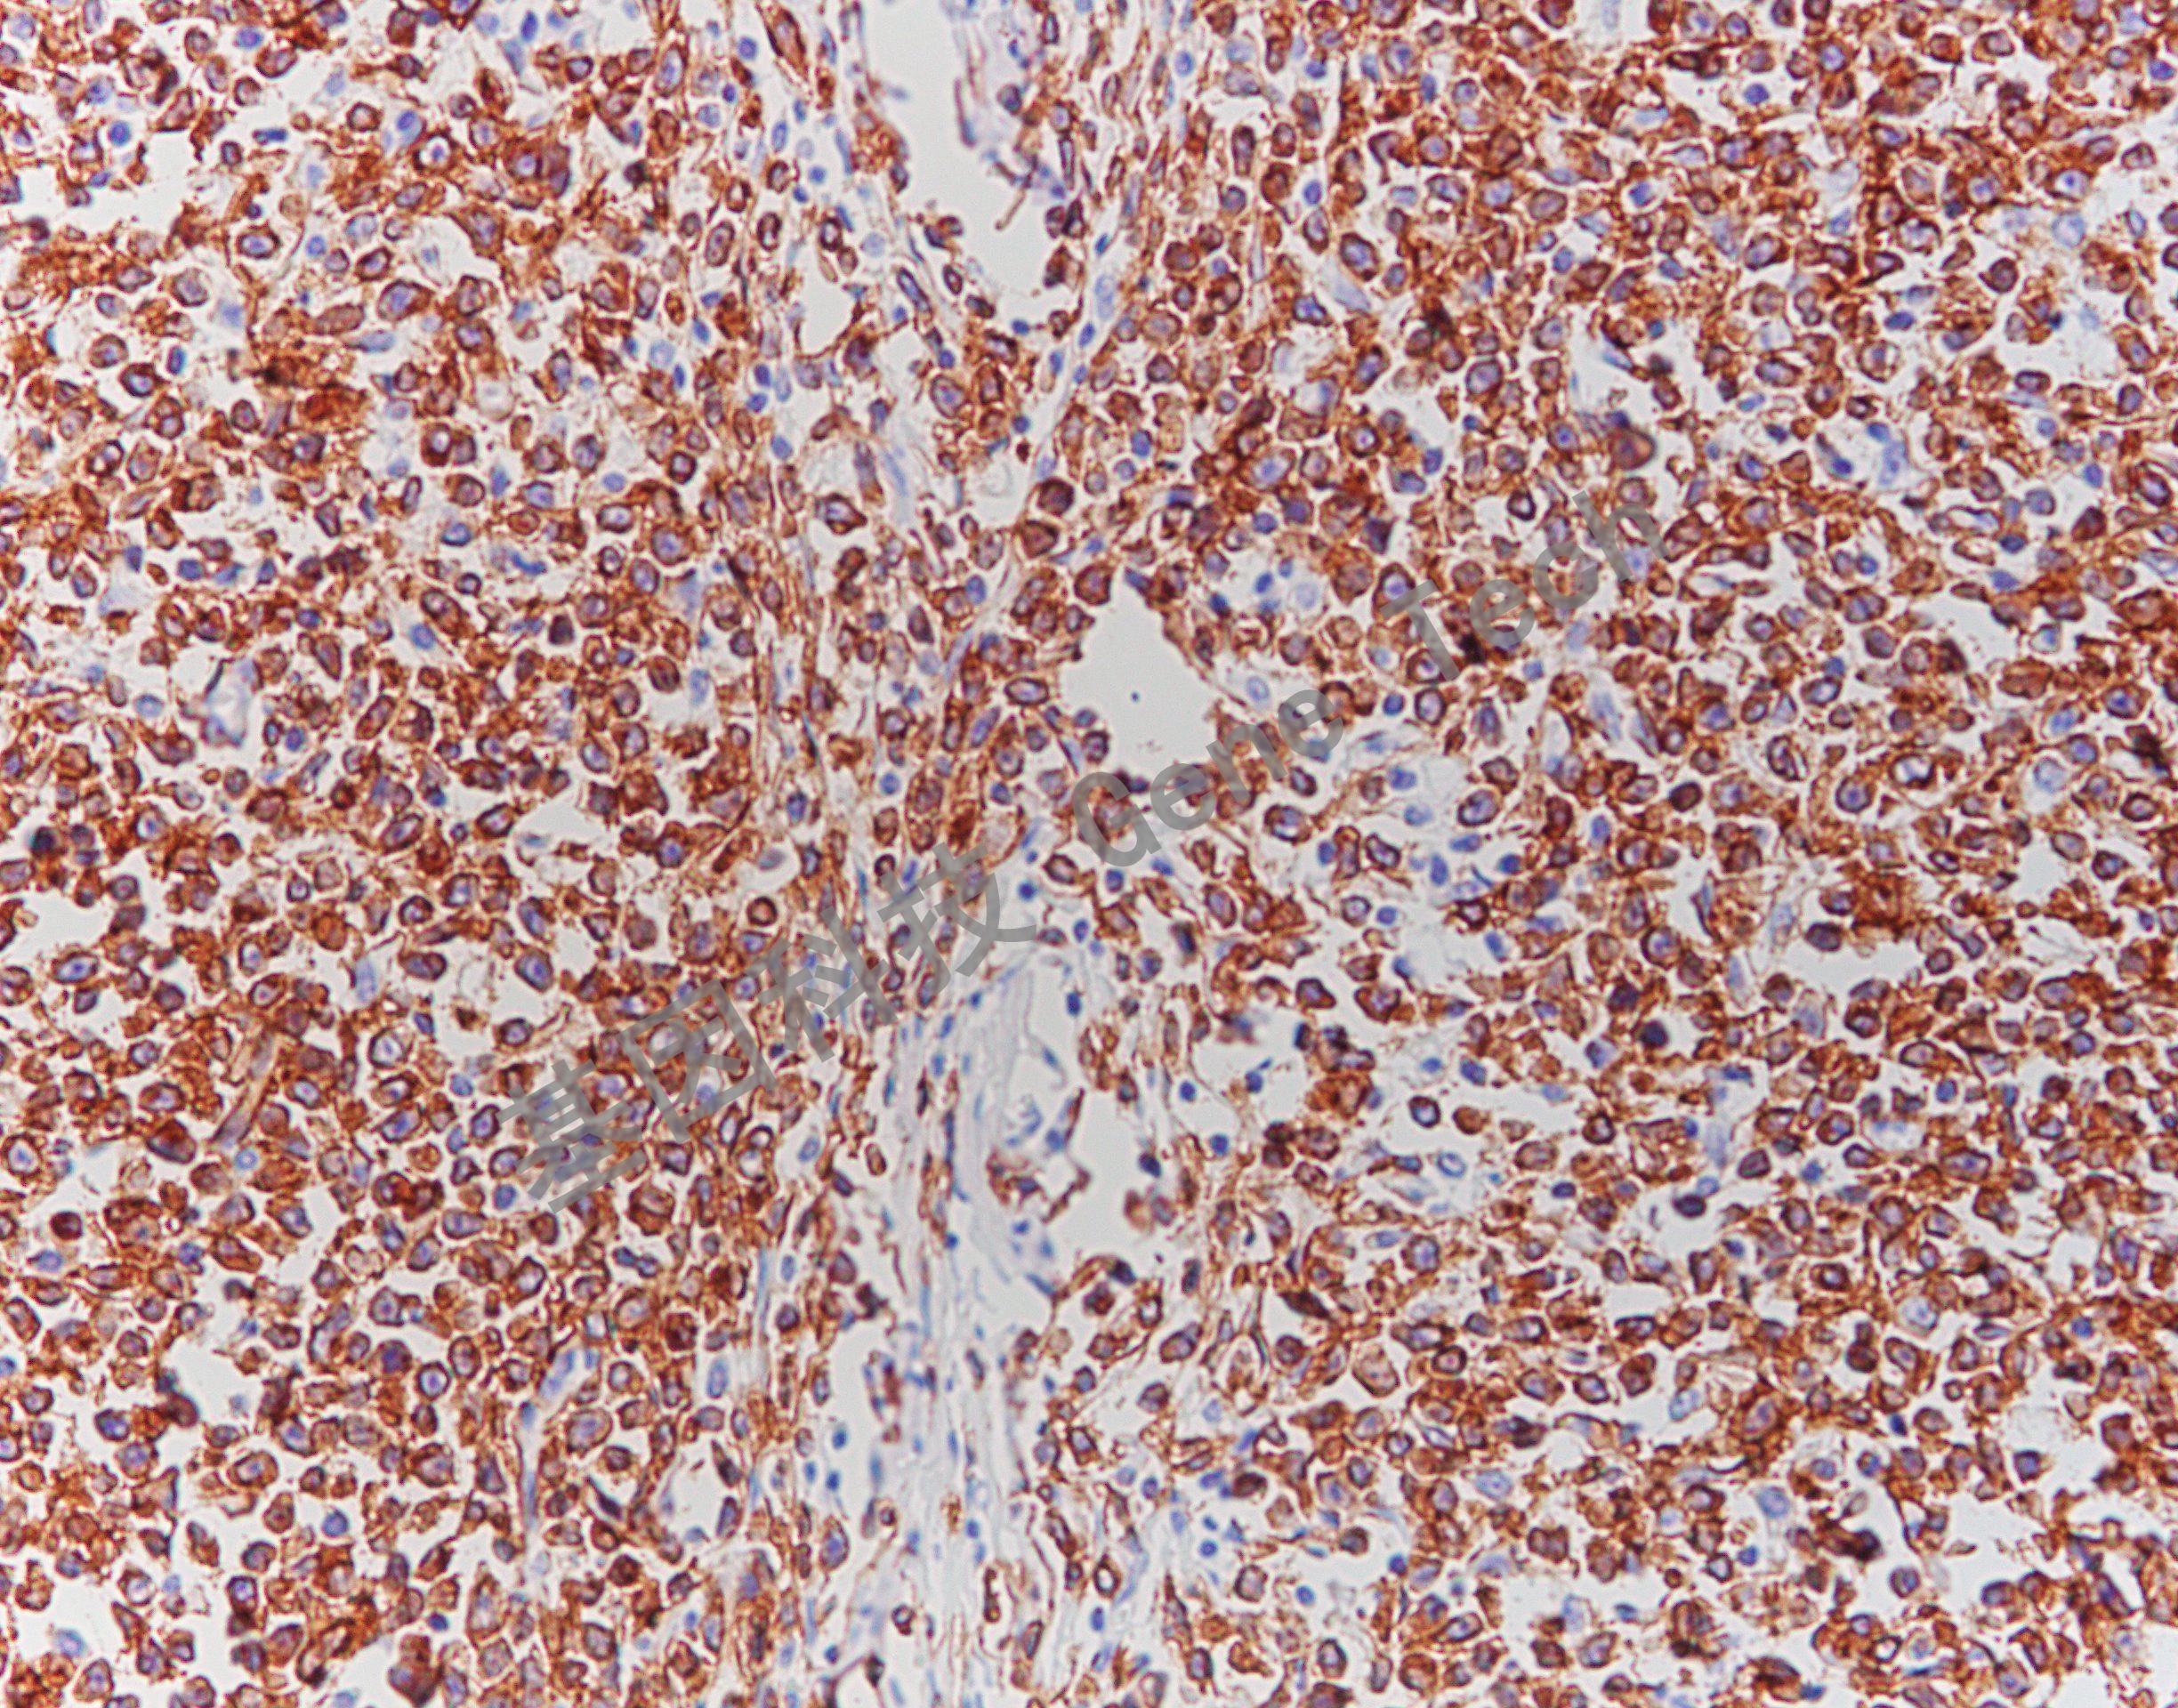

淋巴瘤石蜡切片,用 CD79a(GM7050)染色,细胞膜/细胞浆阳性,DAB 显色。

【阳性部位】细胞膜/细胞浆

CD79a 是广谱 B 细胞标记物,可标记前 B 细胞一直到浆细胞,约 97% 的 B 细胞淋巴瘤可以被标记。